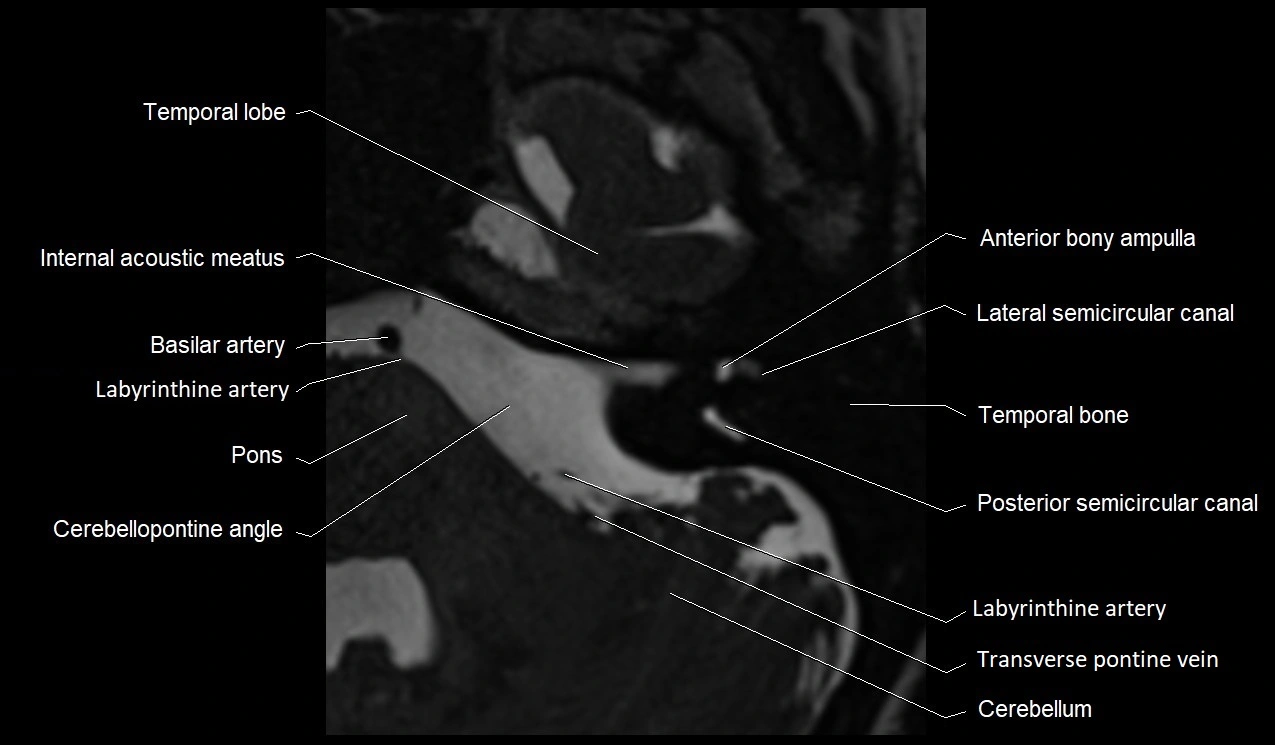

MRI Appearance

• The abducens nerve is a small, thin, linear structure

• Best visualized on high-resolution T2-weighted 3D MRI sequences (e.g., FIESTA or CISS)

• Seen as a hypointense (dark) line running from the brainstem at the pontomedullary junction, traversing the prepontine cistern, and entering Dorello’s canal under the petrosphenoidal ligament, then into the cavernous sinus, and finally the orbit

• May be challenging to visualize in standard MRI due to its small size

• Pathology may be inferred by absence, displacement, or enhancement of the nerve